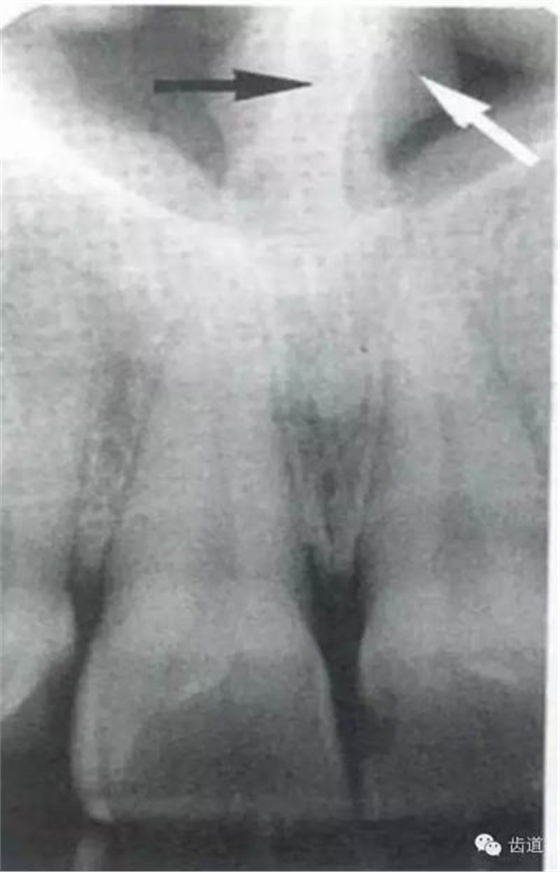

在兩個(gè)中切牙牙根之間或稍上方,多呈橢圓形密度低的影像,切牙孔影像可重疊在一側(cè)中切牙牙根尖處,易誤認(rèn)為根尖周病變,可視牙周膜和骨硬板是否完整加以鑒別

位于兩側(cè)中切牙牙根之間,由牙槽突向上,呈直線狀密度低的影像。其兩側(cè)為密度高的影像,為兩側(cè)上頜骨腭突的致密骨層。

鼻腔位于上切牙根尖的上方,顯示為對(duì)稱性半圓形密度低的影像,其中間被一密度高的骨隔分開為鼻中隔